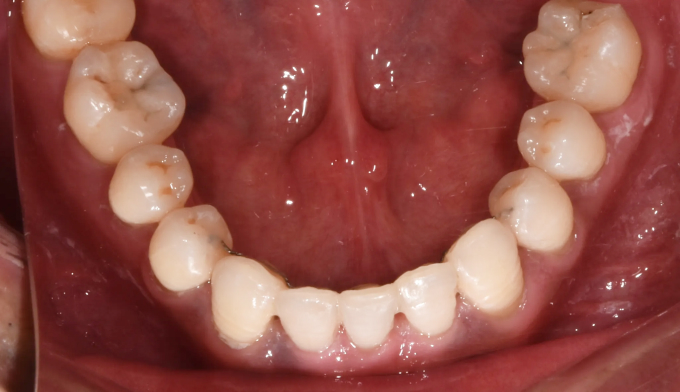

그동안 구강관리 소홀로 아래앞니 하나가 충치로 인해 소실되었으며, 동시에 골격의 주걱턱 경향으로 인해 앞니가 거꾸로 물리는 상황입니다. 아래앞니 빈공간을 임플란트나 크라운과같은 보철치료로 마무리 할 수도 있지만 교정치료를 통해 공간을 메운다면 동시에 거꾸로 물리는 앞니도 개선 가능하므로 교정치료가 보철치료보다 훨씬 효과적인 치료라고 볼 수 있습니다. 환자분의 교정치료에 대한 협조도와 이해도가 높아 비교적 이른 시간내에 교정치료가 마무리되어 매우 만족해 하셨던 케이스입니다. 총 교정기간은 14개월 소요되었습니다.